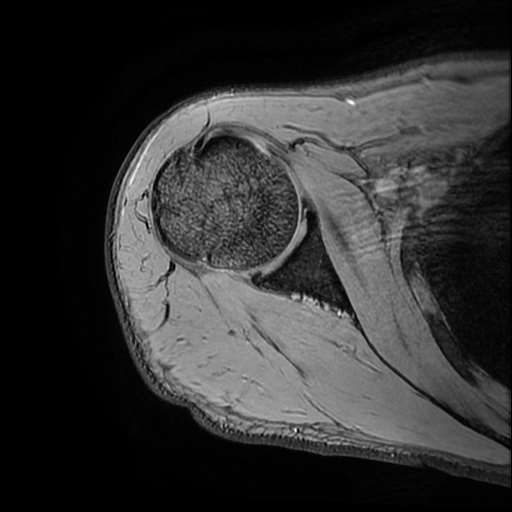

오른쪽 어깨 와순파열 및 점액낭염이 보인다고 하는데 상태를 알고 싶습니다

MRI 사진상 와순파열 점액낭염 등이 있다고 하는데..심한 상태인가요?

MRI상 와순파열, 회전근개 부분파열 등이 있으며 일부 염증소견이 있습니다.

주사, 약물, 물리치료 등에 통증이 호전을 보인다면 경과관찰을 해볼 수도 있겠지만 어깨관절의 불안정성 및 통증이 심하신 상태라면 관절경을 이용하여 수술적 치료를 받으시는 것을 추천드립니다.